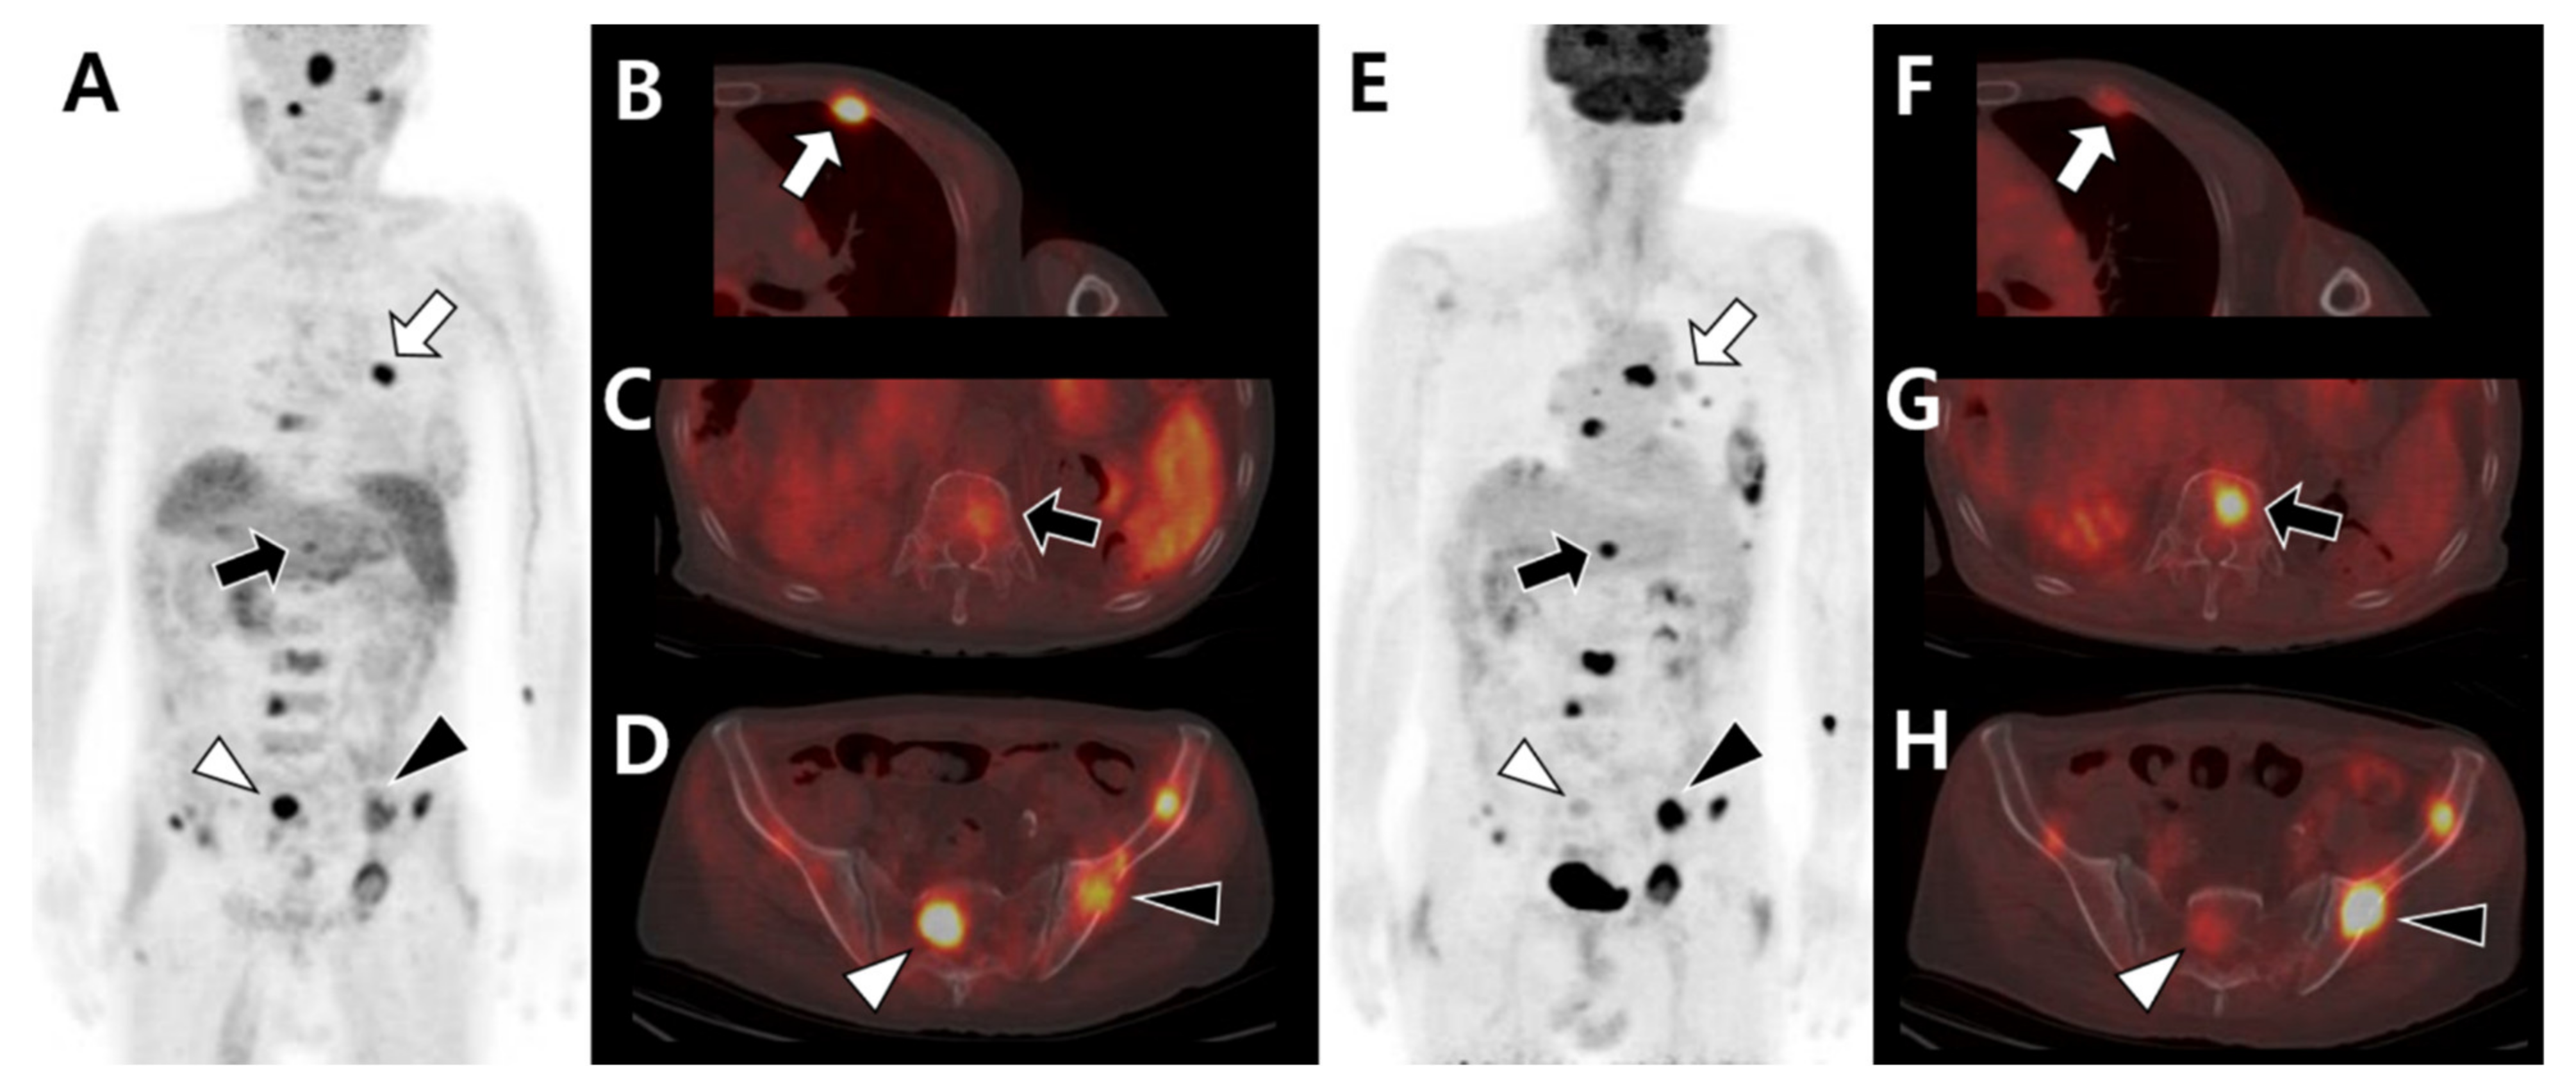

3.1. Multimodal Imaging According to the Primary Tumor Site and Histologic Type

3.2. Multimodal Imaging According to the Differentiation Status of the Primary Tumor